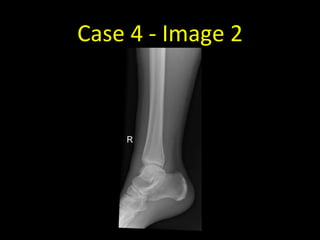

Case 4

• 40 year old with inversion injury of the right ankle

Case 4 - Image 2

• AP and lateral radiographs of

the right ankle

• There is a minimally displaced

spiral fracture of the right

distal fibula at the level of the

syndesmosis